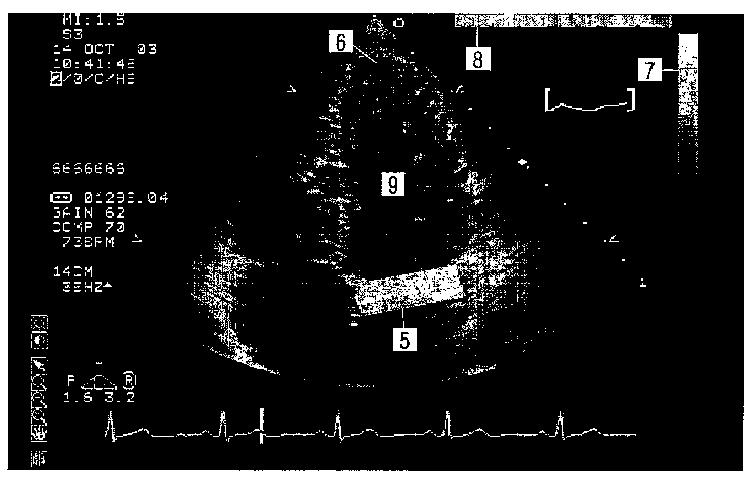

虚血性心疾患の超音波診断方法及び装置